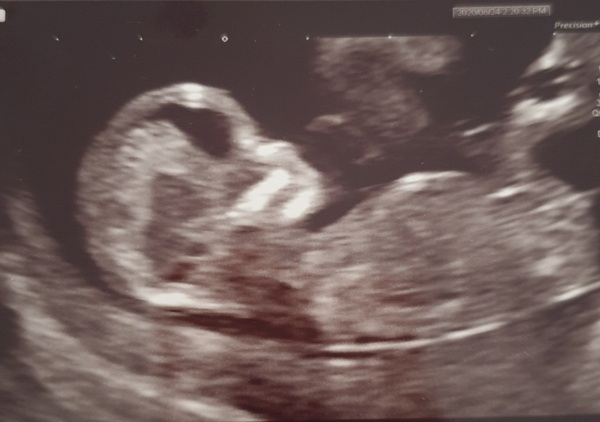

Ladies thank you so much for your good luck wishes...they worked. Baby is measuring a few days ahead according to the last 2 scans so growing well 🤣 they've put me at 12+4 today. Due date is 4th March so I'll update the list soon. Im so bloody relieved. I've never been this pregnant before 🎉🎉

@DanceM1 congratulations what a lovely pic xx

@DanceM1 ahh what an amazing picture and great your past that big milestone 🥰 I've already provisionally booked in the date we'll be getting the gender scan at 16weeks (4th October) - I need time to get used to it if it's a girl, obviously happy with any healthy baby but I'm so desperate for a boy, no idea what to do with girls 😂

Amazing @DanceM1, great pic too